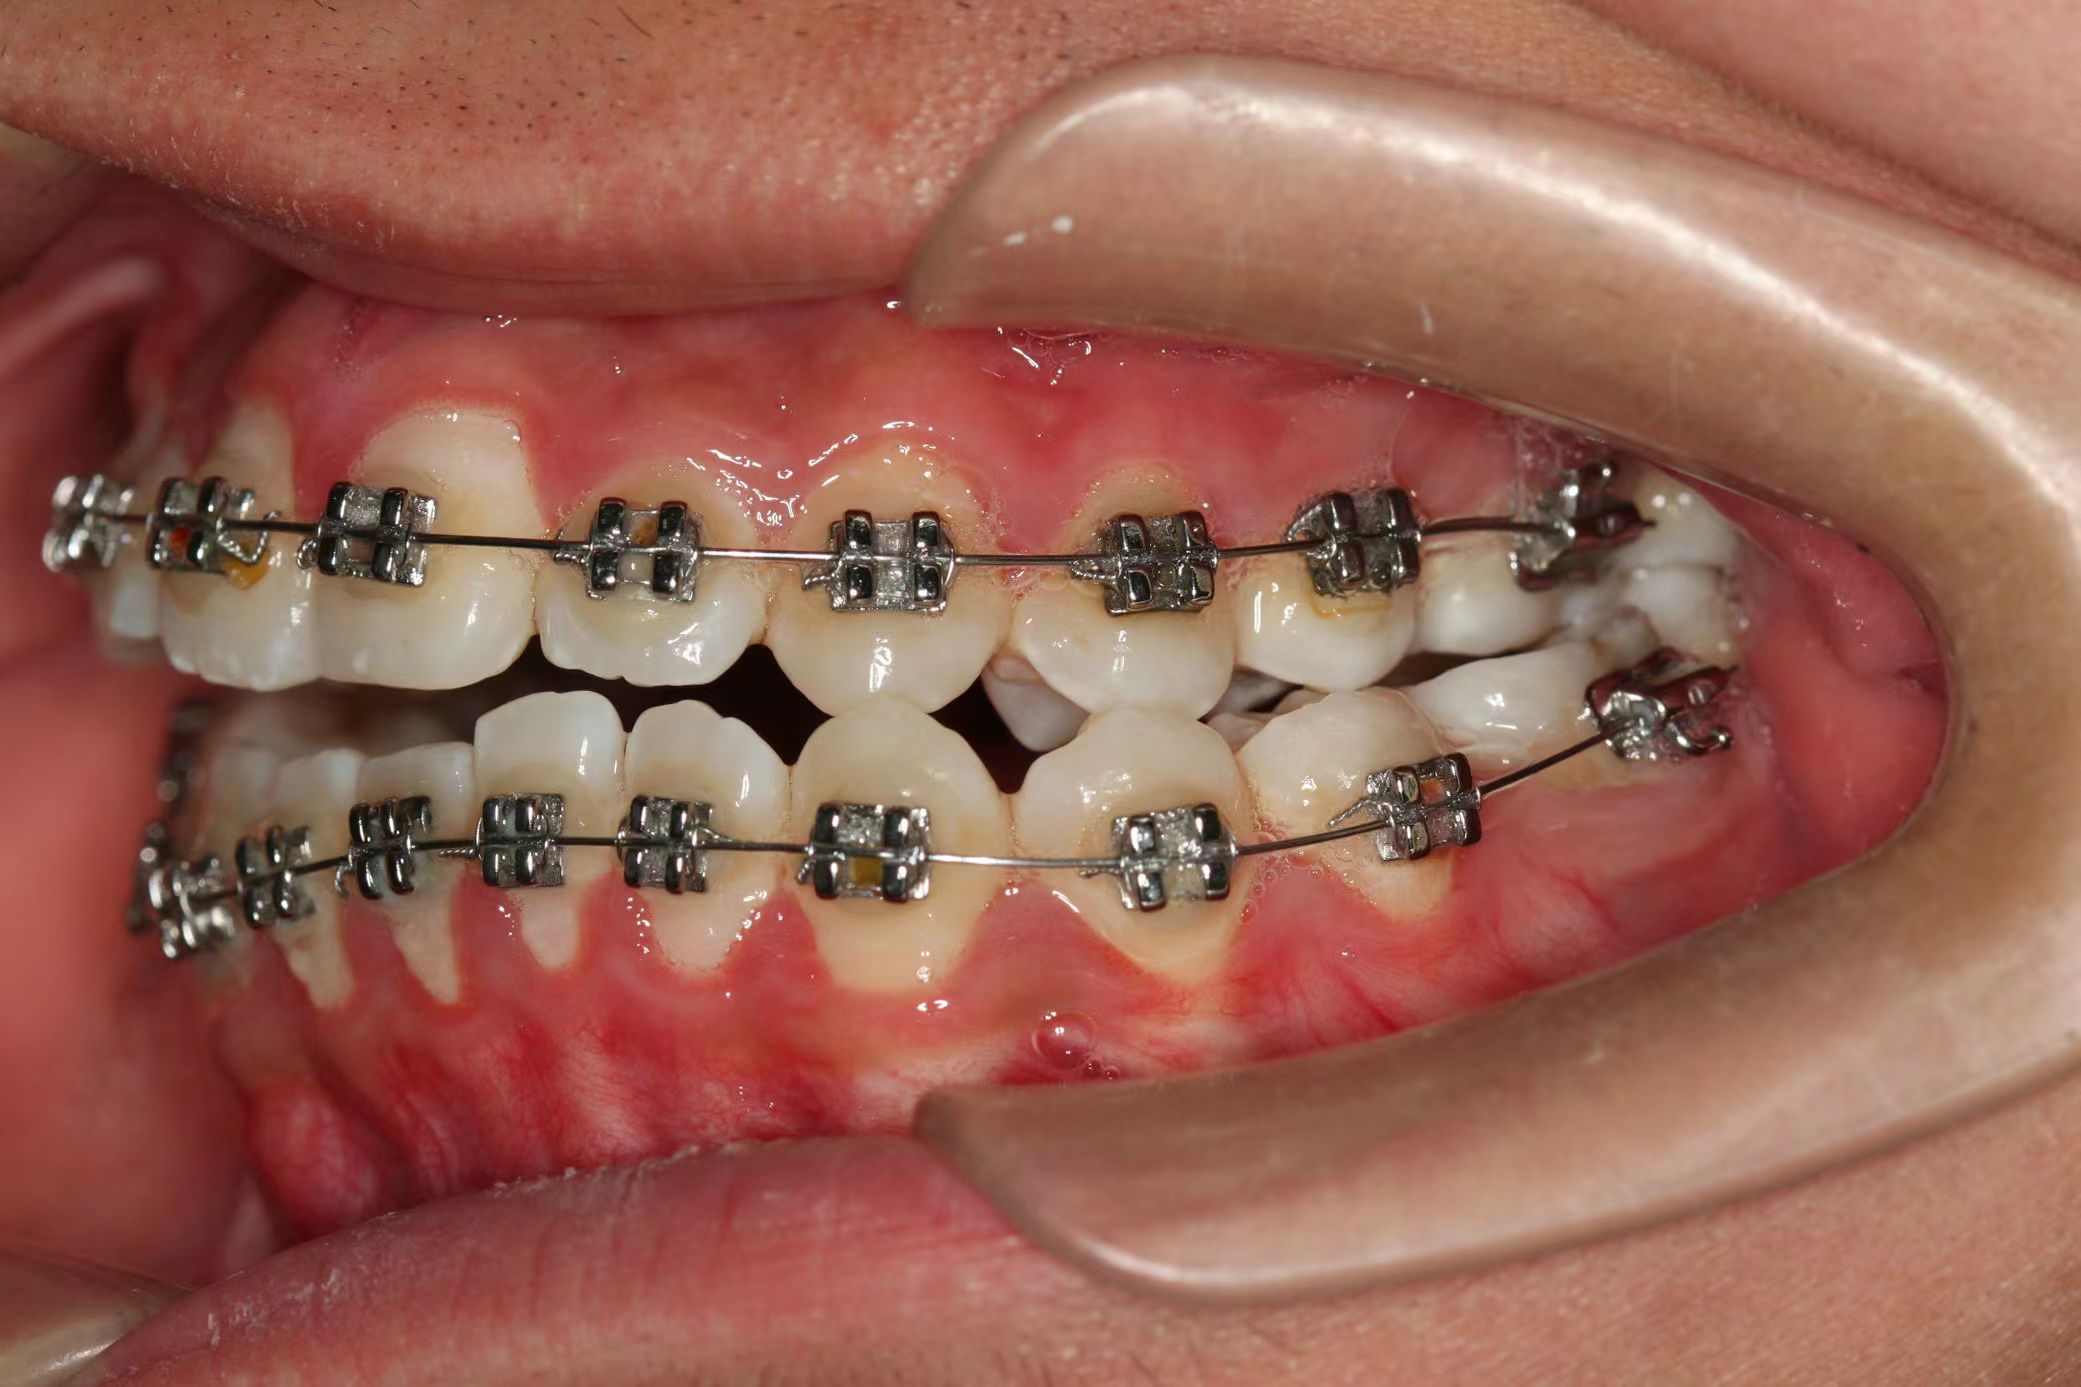

情况:不接受外科手术,在当地做了1年半的矫治,遇到困难无法进行。由外地正畸同行推荐来上海寻求非手术矫治的二手病例。武广增老师接收时的错合畸形情况,呈现严重的骨性反合偏合及侧方开合(图1-图10)。由于推荐其去口腔医院接受正颌外科手术遭到拒绝,武广增老师通过专业的检查、分析,制定一套详细的治疗计划,采用了磨牙推进器技术、武式辅弓技术等特色正畸手段获得明显效果(图2-1~图2-9)。治疗结束后也拍摄了相关照片(图3-1~图3-9)。

矫治前

图3